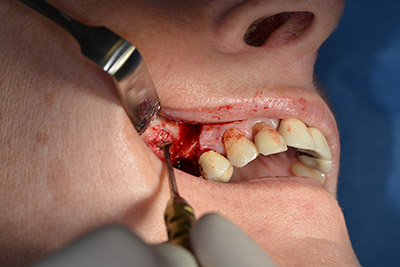

The classic incision (crestal, buccal relief) and the preparation of the mucoperiosteal flap enabled a good overview.

Sky implants (bredent) were used in this case. The surgical protocol of these, specify pilot drilling at about 1200 rpm (Fig. 9).

The following holes were drilled at a reduced speed of 300 rpm. The Implantmed demonstrated its true capability at this stage. The surgical protocol can be preset – the various positions can be selected simply by pressing the “P” position of the foot control (Fig. 10 to 11).